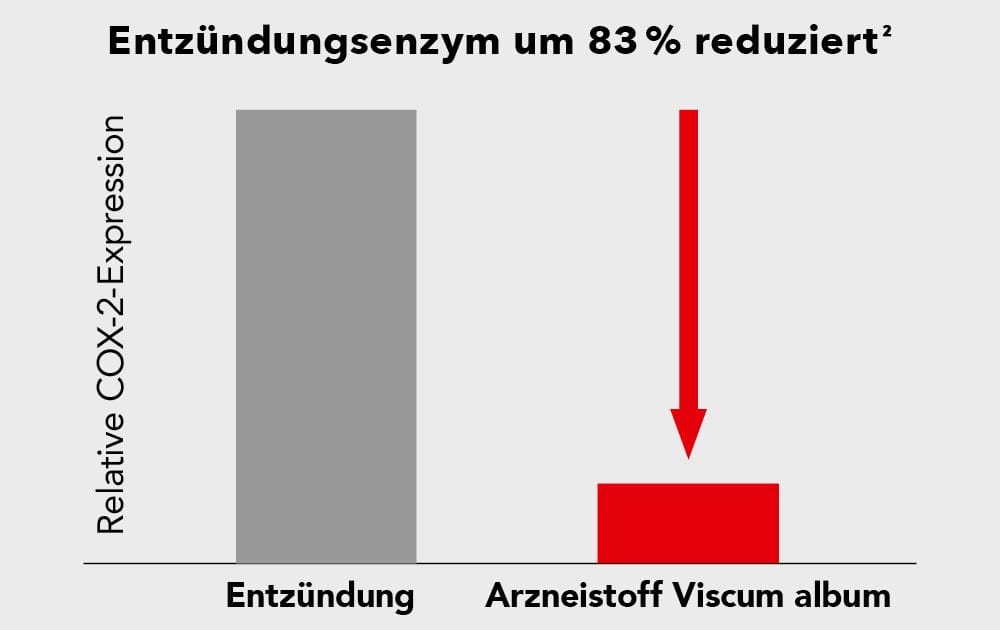

Die Erkenntnisse zum Wirkstoff Viscum album schienen diese Voraussetzungen bestens zu erfüllen. Denn dieser wirkt nicht nur schmerzlindernd. Er hat außerdem in Laborstudien eine signifikante Reduktion eines Entzündungsenzyms um 83% gezeigt.²

So wussten sie, dass Viscum album-Zubereitungen neben ihrer Anwendung in der Krebstherapie auch erfolgreich bei der Behandlung verschiedener entzündlicher Erkrankungen eingesetzt wurde und stellten so die Hypothese auf, dass Viscum album eine entzündungshemmende Wirkung hat.²

Das Geniale: Forscher machten sich daraufhin diese beiden Eigenschaften auch für eine ganz andere Therapie zunutze! Sie stellten fest, dass der Wirkstoff Viscum album aufgrund des speziellen Mechanismus rund um den programmierten Zelltod sowie aufgrund seiner entzündungshemmenden Wirkung nicht nur in der Krebstherapie, sondern auch bei Arthrose helfen kann⁵. Bevor wir jedoch das Geheimnis um die faszinierende Arthrose-Behandlung mit Viscum album lüften, ist es wichtig zu verstehen, wie und warum Millionen Deutsche an Arthrose leiden.